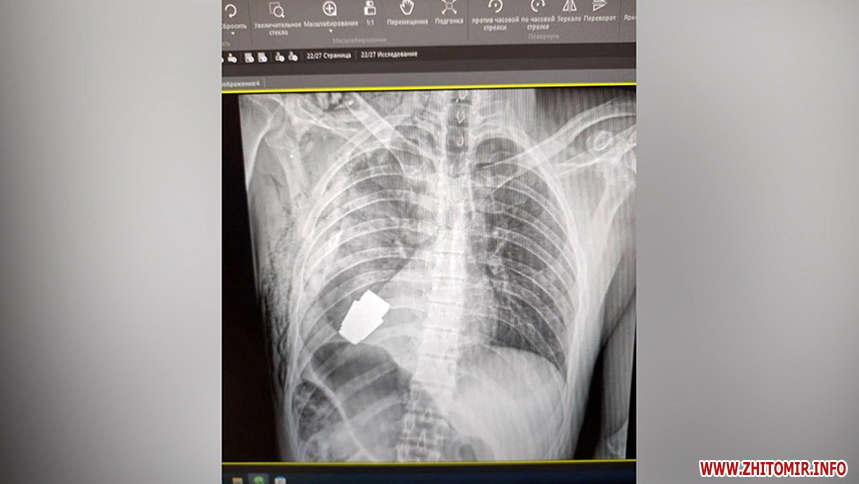

Це знімок військовослужбовця: ворожа граната ВОГ не розірвалася у його тілі. Лікарі під наглядом саперів успішно видалили боєприпас.

«Залетіла міна у черевну порожнину і не розірвалася, з масивним пошкодженням печінки і товстої кишки. Поступив до нас з приводу планового оперативного лікування – закриття товстокишкової нориці», – розповідає завідувач відділення стаціонару в приватній клініці «Медібор» Іван Невмержицький.